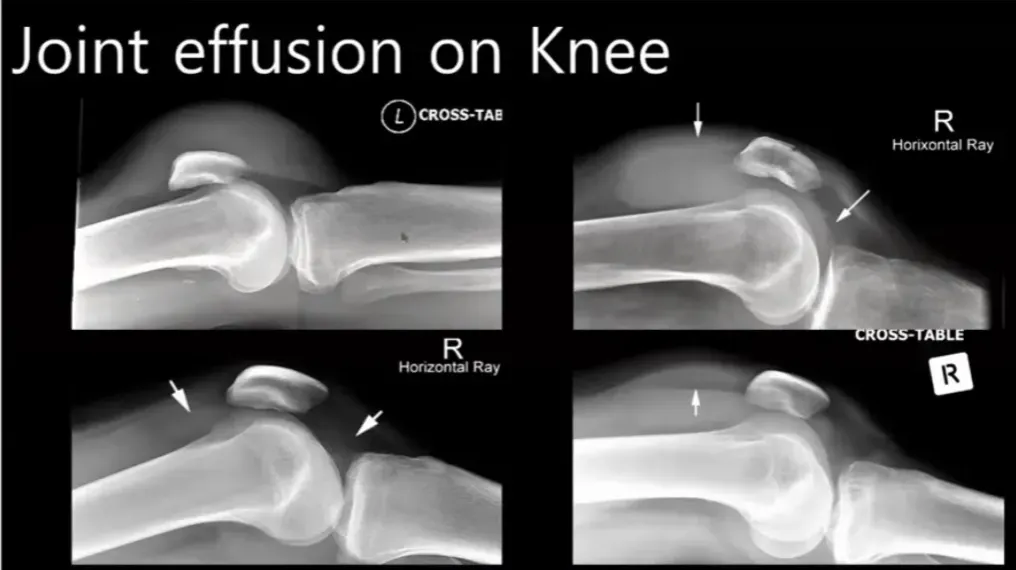

프렉처와 관련된 소프트 티슈는 중요하지 않으며, 엑스레이를 통해 니조인트의 조인트 캡슐의 형태를 확인할 수 있다. 73

조인트 이퓨전이 양이 많을 경우, 엑스레이에서 명확하게 나타나며, 적은 경우에도 파텔라 위쪽에서 발견될 수 있다. 77

조인트 이퓨전이 발견되면, 이는 트라우마 환자의 경우 혈액 손상이 있을 가능성이 높다고 판단된다. 80